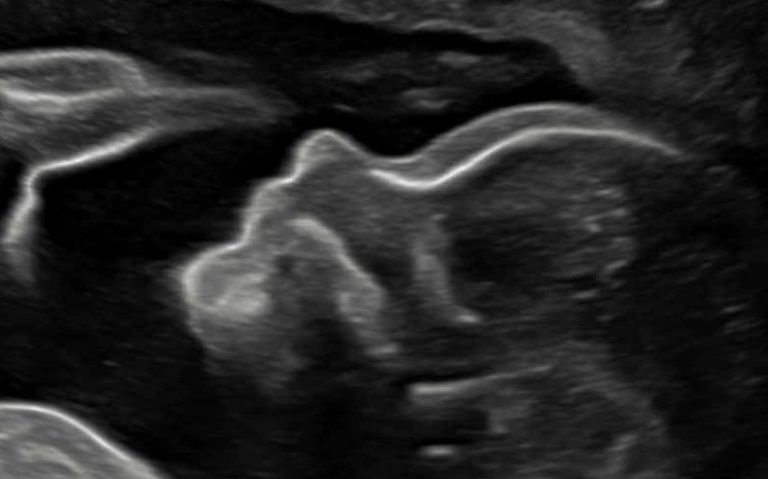

Schwangerschaft

Wir bieten das gesamte Spektrum an Diagnostik in der Schwangerschaft an. Von der Mutterschaftsvorsorge inkl. CTG bis zur Pränataldiagnostik.

- Ersttrimester-Screening inkl. Zusatzmarkern (FMF London-Zertifizierung)

- Präeklampsie-Screening (FMF London-Zertifizierung)

- nicht-invasiver Pränataltest (NIPT)

- erweiterte Fehlbildungsdiagnostik "Feindiagnostik" (DEGUM II)

- Abklärung bei auffälligem Ultraschall, Fehlbildungen in der Familie oder individuell erhöhtem Risiko für Fehlbildungen (DEGUM II)

- Doppler-Sonographie

- diagnostische Punktionen: Chorionzottenbiopsie und Amniozentese